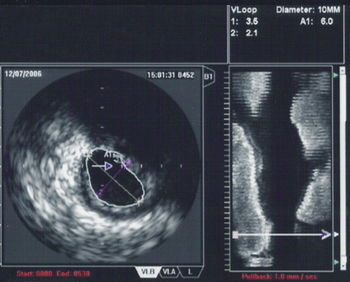

The ultrasound catheter tip is slid in over the guidewire and positioned, using angiography techniques so that the tip is at the farthest away position to be imaged. The sound waves are emitted from the catheter tip, are usually in the 20-40 MHz range, and the catheter also receives and conducts the return echo information out to the external computerized ultrasound equipment which constructs and displays a real time ultrasound image of a thin section of the blood vessel currently surrounding the catheter tip, usually displayed at 30 frames/second image.

The guide wire is kept stationary and the ultrasound catheter tip is slid backwards, usually under motorized control at a pullback speed of 0.5 mm/s. (The motorized pullback tends to be smoother than hand movement by the physician.)

While the routine use of IVUS during percutaneous coronary intervention does not improve short term outcomes,[4] there are a number of situations in which IVUS is of particular use in the treatment of coronary artery disease of the heart. In particular in cases when the degree of stenosis of a coronary artery is unclear, IVUS can directly quantify the percentage of stenosis and give insight into the anatomy of the plaque.

When using IVUS to determine whether an individual's left main disease is clinically significant, in terms of the desirability of physical intervention, the two most widely used parameters are the degree of stenosis and the minimal lumen area.[6] A cross sectional area of ≤7 mm² in a symptomatic individual or ≤6 mm² in an asymptomatic individual[7] is considered to be clinically significant and warrants intervention to improve one-year mortality. However, these exact cutoffs are up for debate and different cutoff cross-sectional areas may be used in practice depending on differing interpretations of the trial data.